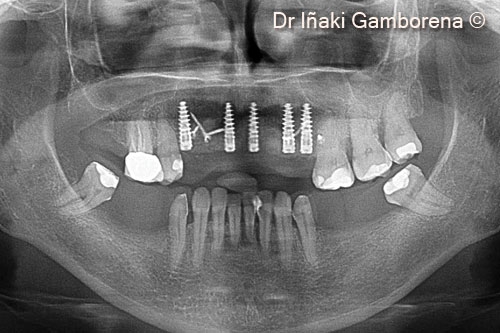

Một bệnh nhân nữ (53 tuổi) muốn làm phục hình cố định hàm trên bằng implant.